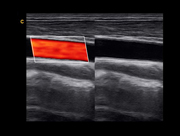

Carotid,BBC Mode